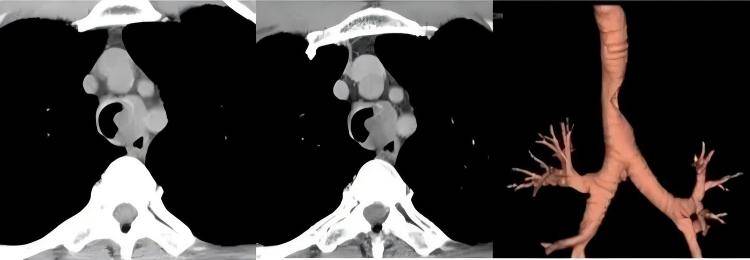

案例1:左主支气管 1.5cm 错构瘤(电圈套器 + 活检钳清除)

患者情况:37 岁女白领,体检发现左主支气管肿物,最大径 1.5cm(成人左主支气管正常内径 0.9-1.2cm),已造成气道严重狭窄,伴偶尔干咳,未出现明显呼吸困难。

手术操作:先经支气管镜活检明确为良性错构瘤(血供不丰富),再用适配型号电圈套器套扎肿物根部,残余组织通过活检钳分次清除,同时用负压吸引避免碎屑堵塞气道。

治疗效果:手术耗时 40 分钟,全程出血<3ml,术后 2 小时患者呼吸顺畅,可下床活动,住院 3 天康复出院,术后 1 个月复查支气管镜示气道通畅,无肿瘤残留。